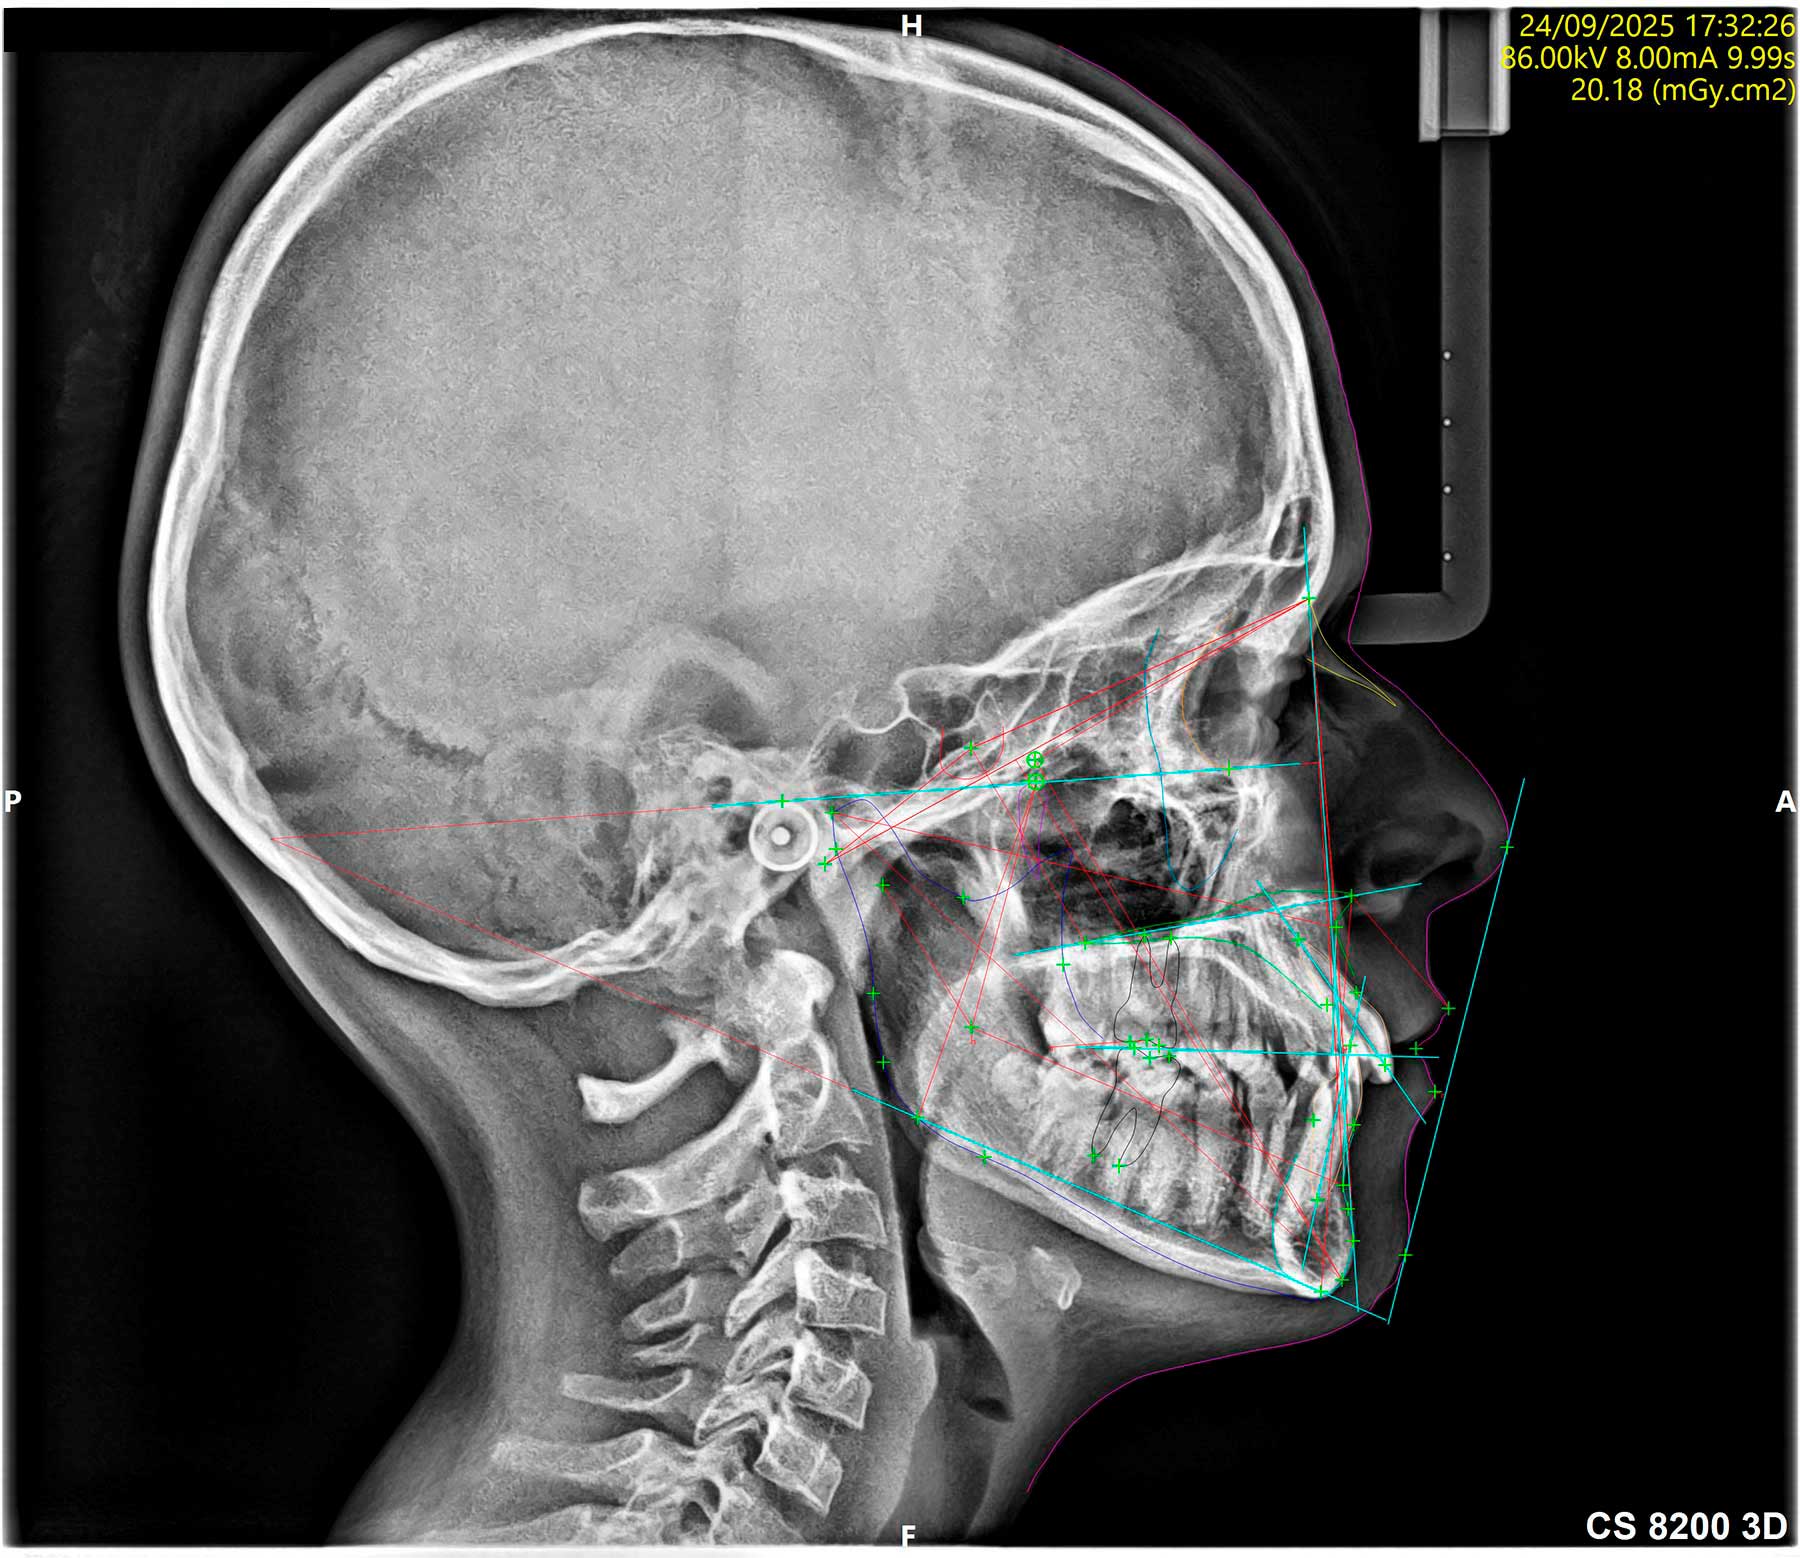

Radiología digital

Reduce en un 80% la radiación que recibe el paciente y permite obtener una imagen de forma instantánea, sin necesidad de revelado. Además, la tecnología digital permite la mejora de la imagen mediante técnicas informáticas. Hemos incorporado además, tecnología 3D mediante un sistema avanzado de Tomografía Computarizada de baja radiación CBCT (la de más baja radiación disponible en el mercado), lo que nos permite determinar la posibilidad de colocación de implantes en la primera visita diagnóstica, así como la detección de patologías asociadas a los maxilares.

Servicio de Tomografía computarizada CBCT, ortopantomografía, telerradiografía y radiografías de ATM al momento

Mediante la radiología digital de baja radiación, podemos valorar estructuras de interés odontológico o craneal, con imágenes 2D o 3D, según sea el caso.